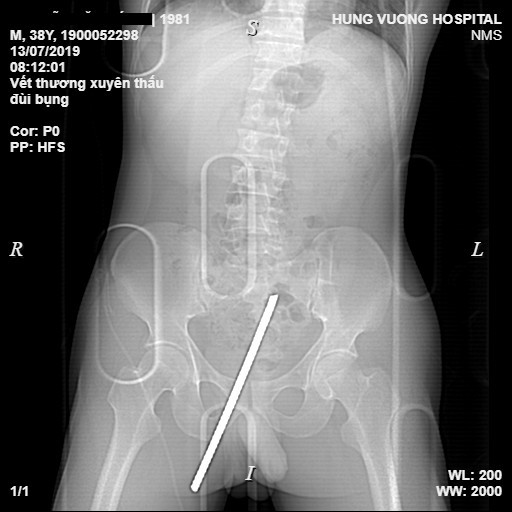

• Ngày 13/7, Bệnh viện đa khoa Hùng Vương (Phú Thọ) cho biết khoảng 8h cùng ngày, các bác sĩ tại đây đã cấp cứu thành công nam bệnh nhân 38 tuổi (ở tỉnh Tuyên Quang) bị một thanh sắt dài khoảng 20 cm đâm xuyên thấu từ đùi phải lên bụng.

Nam bệnh nhân được đưa vào Bệnh viện đa khoa Hùng Vương cấp cứu trong tình trạng đau đớn, mất vận động vùng đùi phải, dị vật xuyên thấu vùng đùi phải, sát gốc "của quý" lên vùng bụng và còn lộ đầu sắt dài khoảng 10 cm.

Thanh sắt xuyên từ gốc 'của quý' lên bụng nạn nhân

Người nhà cho biết bệnh nhân là lái xe chở vật liệu xây dựng, khi nhảy từ trên xe xuống đất đã không quan sát kỹ và bị thanh sắt cắm mốc dưới đất xuyên thẳng vào đùi. Ngay khi xảy ra tai nạn, các công nhân trong công trường đã dùng cưa sắt cưa đứt phần gốc thanh sắt và đưa nạn nhân đến Bệnh viện Hùng Vương cấp cứu.

Kết quả chụp chiếu cận lâm sàng của bệnh nhân cho thấy hình ảnh dị vật kim khí trong phần mềm dưới da vùng bẹn mu bên phải, sát dương vật, xuyên chéo lên đi dọc theo thành bụng dưới rốn trái.

Kíp mổ gồm các bác sĩ tim mạch, tiêu hóa, ngoại chấn thương và gây mê… đã hội chẩn, đánh giá sơ bộ về nguy cơ gây tổn thương ổ bụng do thanh sắt lớn gây ra cho bệnh nhân và chỉ định phẫu thuật xử lý vết thương. Sau 3 giờ đồng hồ phẫu thuật, các bác sĩ đã lấy dị vật ra khỏi cơ thể bệnh nhân. Bệnh nhân được chuyển phòng Hồi sức cấp cứu tiếp tục điều trị.